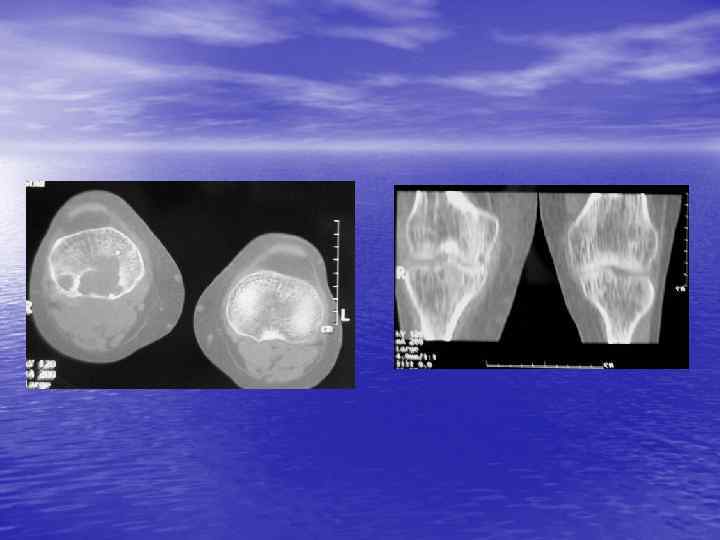

Структурный анализ Оценка основных макроскопических признаков: - положение - форма - размеры - характер контуров и структур патологически измененных участков

Структурный анализ

Преимущества спиральной КТ: ü Возможность проведения исследования с болюсным ü ü ü ü ü контрастированием Высокая разрешающая способность; Высокая скорость исследования; Получение высококачественных изображений костных структур; Возможность обследования всего тела; Возможность проведения исследования больных под наркозом; Возможность детальной оценки состояния крупных и периферических сосудов в условиях искусственного контрастирования; Высокая информативность метода при черепномозговых травмах в остром периоде; Ранняя диагностика ишемических и геморрагических инсультов; Метод выбора для диагностики заболеваний легких; Планирование лучевой терапии.